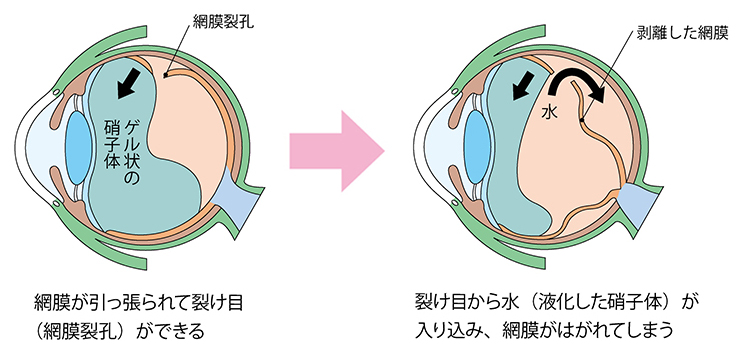

網膜裂孔とは、眼球の奥にありフィルムの役割を担っている「網膜」に割れ目や穴(孔)が生じた状態です。

網膜裂孔は硝子体の変性や萎縮によって起こる「萎縮性」と、硝子体が網膜を引っ張ることで起こる「牽引性」に分けられます。そのうち、牽引性の網膜裂孔が特に網膜剥離へと進展する可能性が高くなります。

網膜剥離とは、網膜が眼球壁から離れた状態です。

網膜に割れ目・穴が生じている段階に留まるものを「網膜裂孔」、網膜が部分的にでも剥がれているものを「網膜剥離」と区別します。網膜剥離の方が重症であり、剥がれた部分では光を感じにくくなります。

網膜裂孔の主要な原因は、加齢です。健康な人でも、中高年になると目の中にあるゼリー(硝子体)が縮み始めます。網膜が硝子体に引っ張られることで網膜に裂け目や穴が生じます。

網膜剥離のほとんどは、網膜裂孔から進展して発症します。つまり、網膜剥離の原因は網膜裂孔と共通しています。